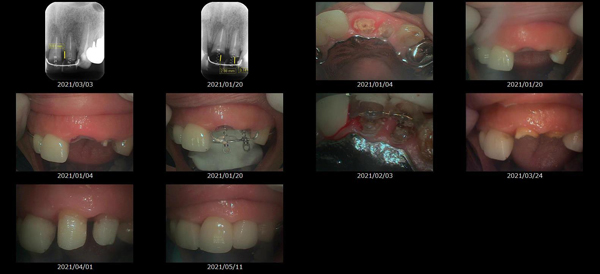

救歯MTM

虫歯が大きくて残せない歯、転倒などの事故により歯が根の深いとこで折れてしまったなどで、抜かざるを得ない歯を、骨の中に埋まっている健全な根を、骨の上に矯正的に引き上げることで、その歯を抜かず温存、救歯できる可能性のある治療方法です。

この特別な診療である救歯MTMは、以下のような特徴があります。

①健全な歯を、歯肉から見える位置にまで引き上げることで

根の治療の成功率を上げることが出来る。唾液には沢山の細菌がいます。唾液が入らない環境での根の治療を(神経の治療)を行うことで神経の治療、根の治療の成功率は格段と上がります。

②骨の上にある歯と土台で支える被せもの製作できる。

被せものを土台だけに頼ることなく、引き上げた健全な歯でも支えることで、歯への被せ物がしっかりと装着できるようになる。

③抜かずに歯を活かすことで、隣の歯を削るブリッジやインプラントにしないで済むことがある。

歯を矯正的に引き上げることで、その歯を救歯できるだけでなく、隣の歯を削るなどの侵襲を回避できる場合がある。

リスク

- > 歯を矯正的に引き上げることで、骨の中の根の長さは短くなりますが、その短さでも安定するという診断をした場合のみ施術になります。 残せる歯、根の長さが短い場合は、この救歯MTMの治療対象とならない場合がございます。

- > 治療期間が数か月~1年に及ぶ場合がある。

- > 費用が自費診療 44,000円 ~ 66,000円

- > 救歯MTMは救歯BTAセラミックと併用治療が必要な場合があります。

症例